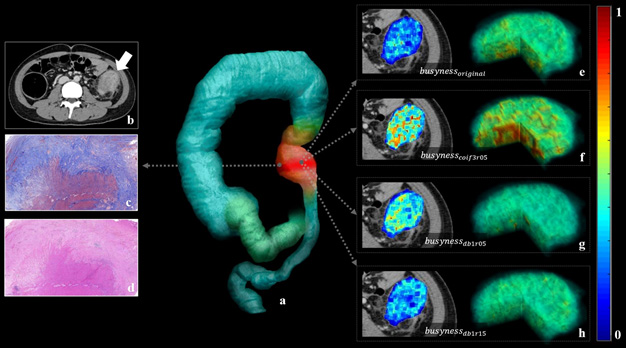

基于CT图像与机器学习评估肠壁纤维化的实例及相应影像特征的展示(该图片已经提交作为期刊封面图片)

克罗恩病(Crohn’s Disease)是一种透壁性炎症性慢性肠病,并发症包括肠壁各层炎症与纤维组织增生导致的肠道狭窄。准确判断克罗恩病患者的肠壁纤维化程度,对其治疗方式、预后与生活质量至关重要。目前临床上缺乏可靠有效的评估方法,医生往往需要综合临床症状、血清学指标、内镜等多种方法评估患者肠壁纤维化程度,主观性较强且严重依赖经验,影响患者治疗效果。该研究提出了一种基于CT图像与机器学习的克罗恩病肠壁纤维化无创评估方法。首先,基于自行开发的影像组学算法从患者CT影像中提取影像特征。其次,采用一系列特征工程技术对特征进行处理,确定与纤维化相关的影像组学特征。最后,基于机器学习方法构建预测模型,并在多中心临床数据上完成验证。结果表明,该方法能够客观准确评估肠壁纤维化程度,性能稳定(AUC接近0.9)且大大优于临床医生评估结果,不受不同中心、扫描设备、病灶部位、炎症与穿透性并发症等影响。